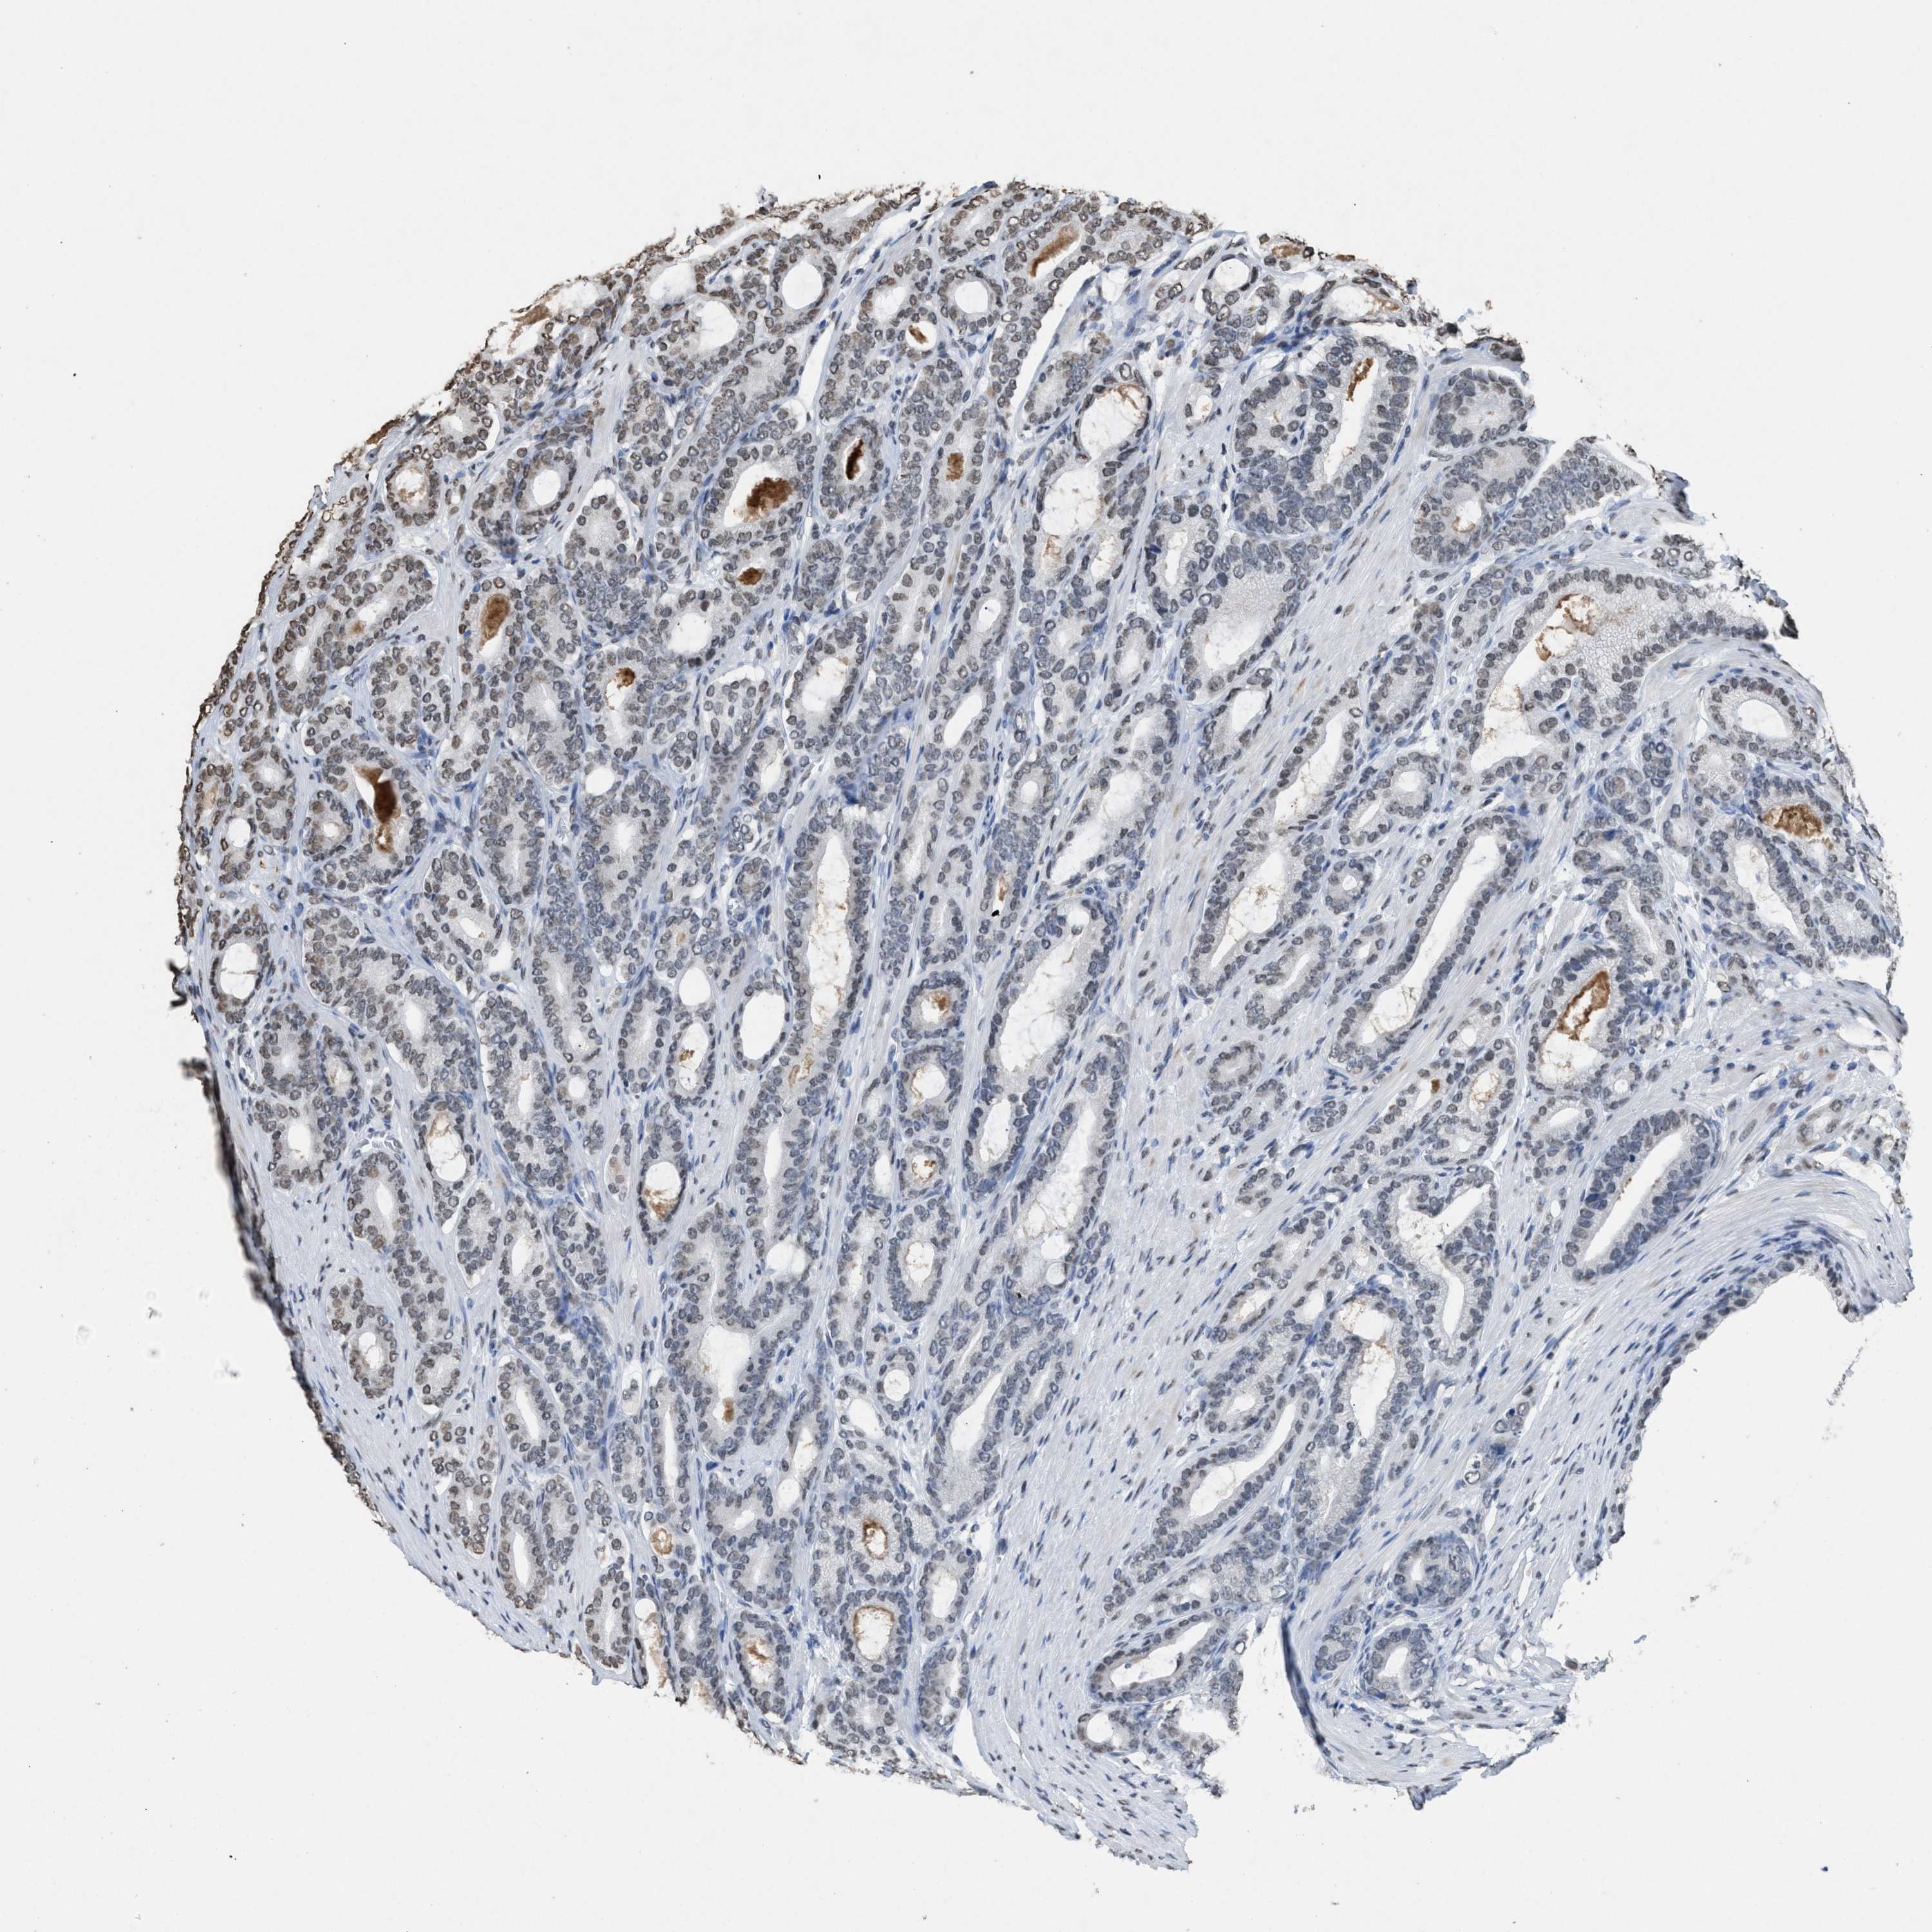

PROSTATE CANCER - Protein expressioni

A mouse-over function shows sample information and annotation data. Click on an image to view it in a full screen mode. Samples can be filtered based on level of antibody staining by selecting one or several of the following categories: high, medium, low and not detected. The assay and annotation is described here.

Antibody stainingi

Antibody staining in the annotated cell types in the current human tissue is reported as not detected, low, medium, or high, based on conventional immunohistochemistry profiling in selected tissues. This score is based on the combination of the staining intensity and fraction of stained cells.

Each image is clickable and will lead to virtual microscopy that enables deeper exploration of all samples and also displays staining intensity scores, fraction scores and subcellular localization as well as patient and tissue information for each sample.

Antibody HPA021816

Antibody CAB002209

Staining

High

Medium

Low

Not detected

Intensity

Strong

Moderate

Weak

Negative

Quantity

>75%

75%-25%

<25%

None

Location

Nuclear

Cytoplasmic/membranous

Cytoplasmic/membranous,nuclear

Adenocarcinoma, High grade

Adenocarcinoma, Low grade

Adenocarcinoma, Medium grade